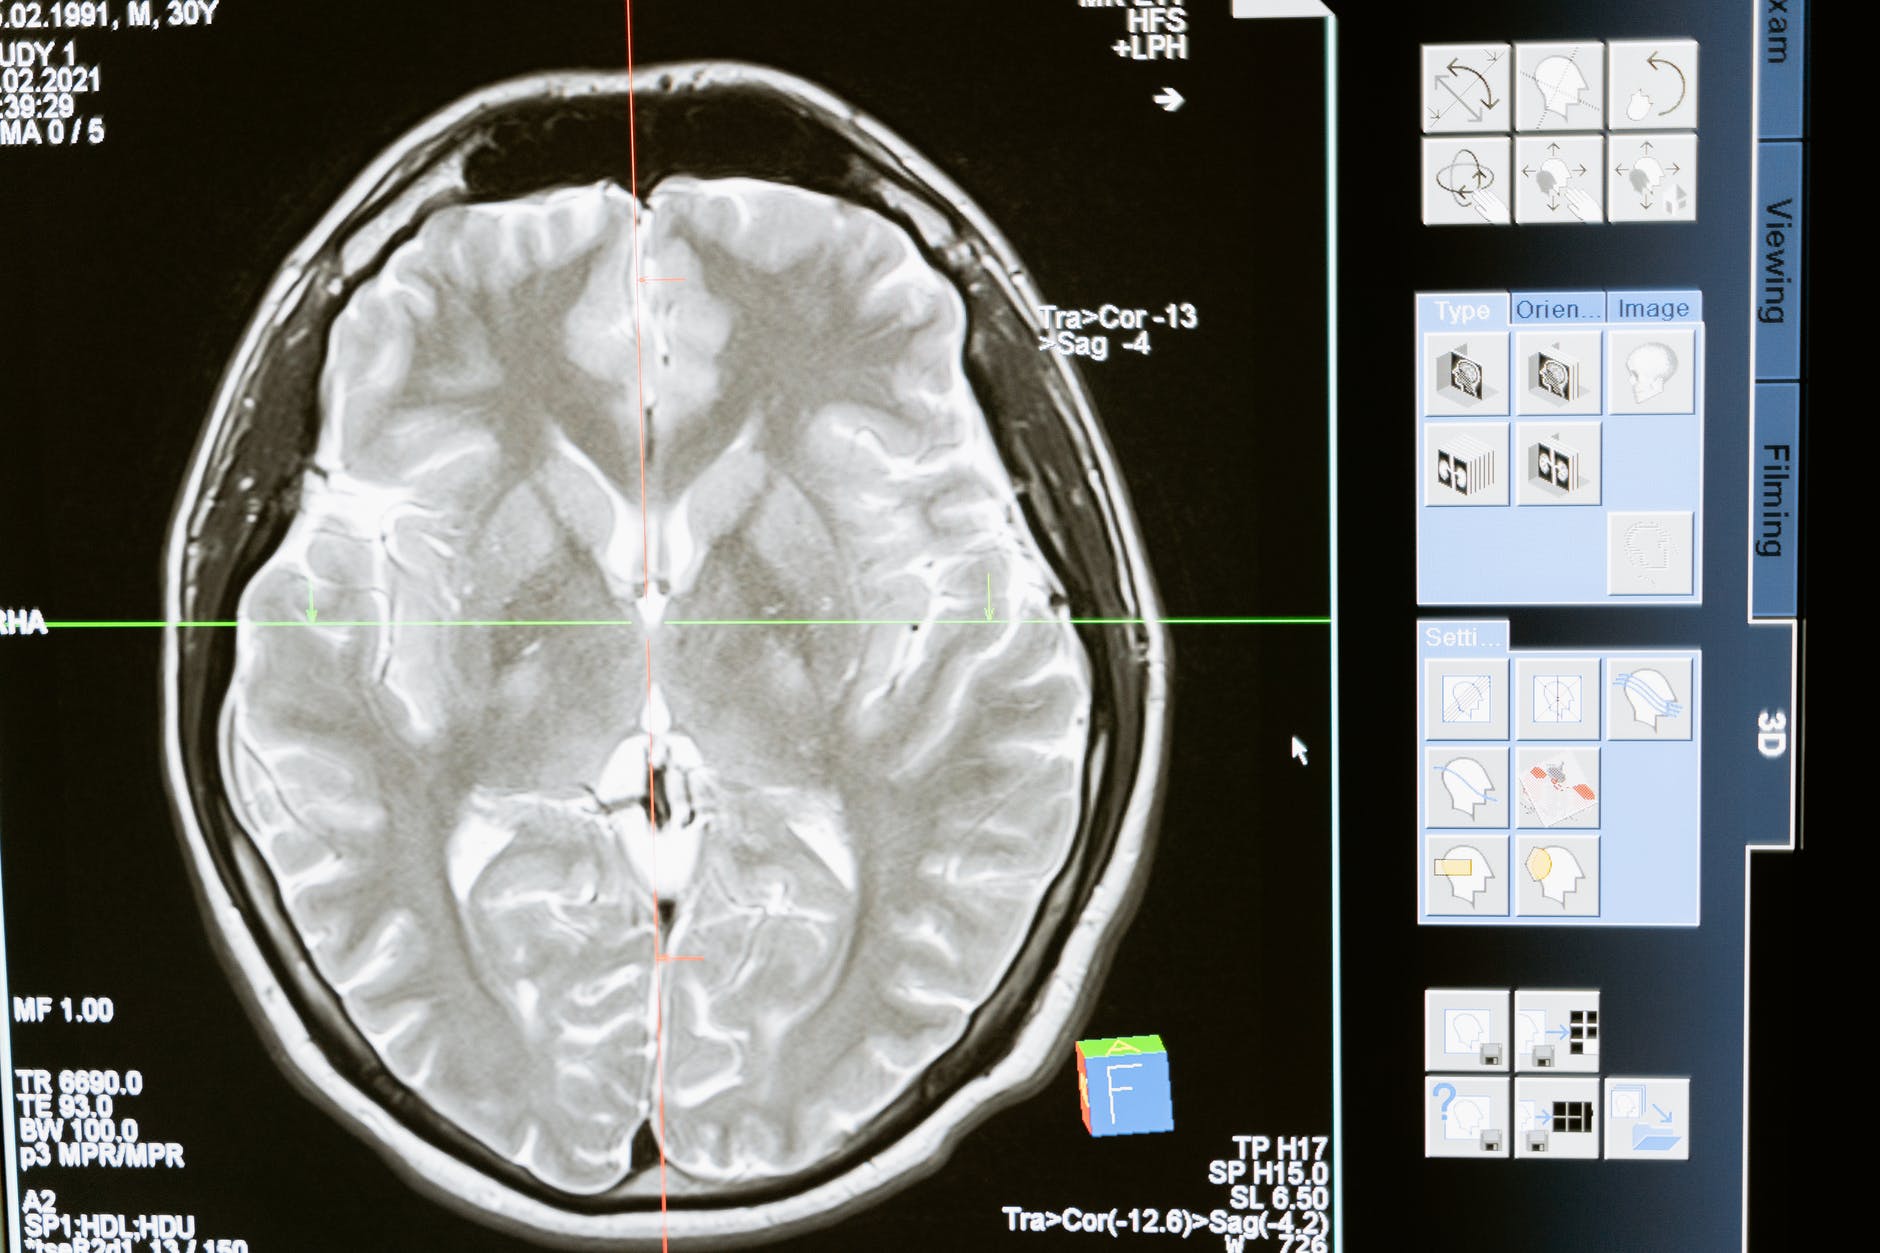

As we get older, we experience an inevitable decline in physical and mental functions. However, the rate of this reduction is dependent on several factors, both genetic and environmental. It has long been contended that there is a relationship between how we use our brains and mental capacity loss. Mind-training, particularly in the form of meditation, has the potential to mediate how we age. There is a great deal of anecdotal evidence that long term meditators retain good mental function throughout their lives; I have even researched the possible link between meditation and resilience to neurodegeneration (dementia). However, progress in this area is limited by two main problems; poor understanding of the mental processes underpinning meditation and the presence of confounding variables.

Despite over eighty years of meditation research, we know relatively little about how long term meditation changes our brain. This problem is compounded because most long-term meditators are found in spiritual traditions; their lifestyles tend to be atypical. For example, committed Buddhists generally eat healthier diets, take less alcohol and are less likely to be found in stressful occupations than the general population; all factors likely to influence health. Despite these problems, some preliminary research suggests that meditation might slow ‘mental ageing’ (age-related mental decline).

Because of the limitations in meditation and mindfulness research, claims about the regulation of I-ENs through mind-training are still speculative. However, there is a good deal of data, some presented in this paper, that suggests meditation may have an essential role in maintaining brain function and structure through the lifecycle.